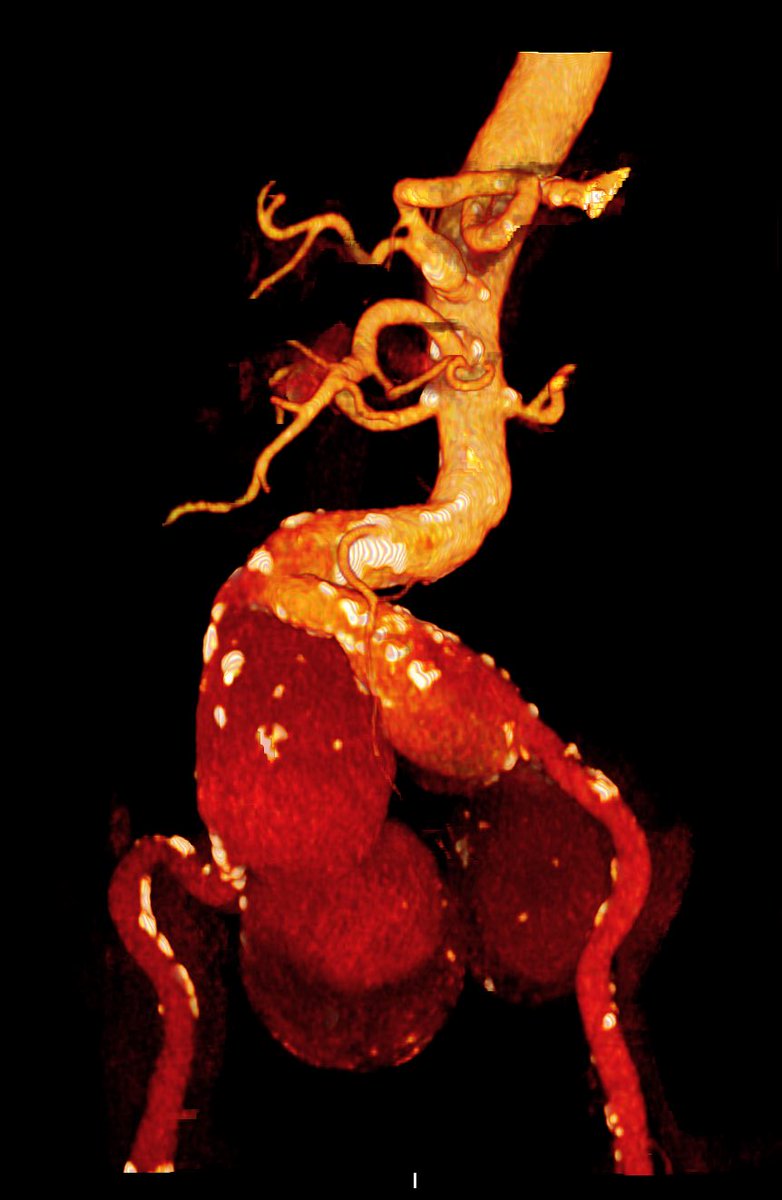

@AndrePoci Congratulations! Beautiful neck. Diseased bifurcation. Tube or bifurcated?

@seleno_glauber We were able to do the infrarenal clamping, it was a stable paciente non rupted.

@AndrePoci Did you achieve a infrarenal approach at first attempt or begun with a supraceliac clamping?

PS: I’ve never seen such a left kidney displacement. Amazing.